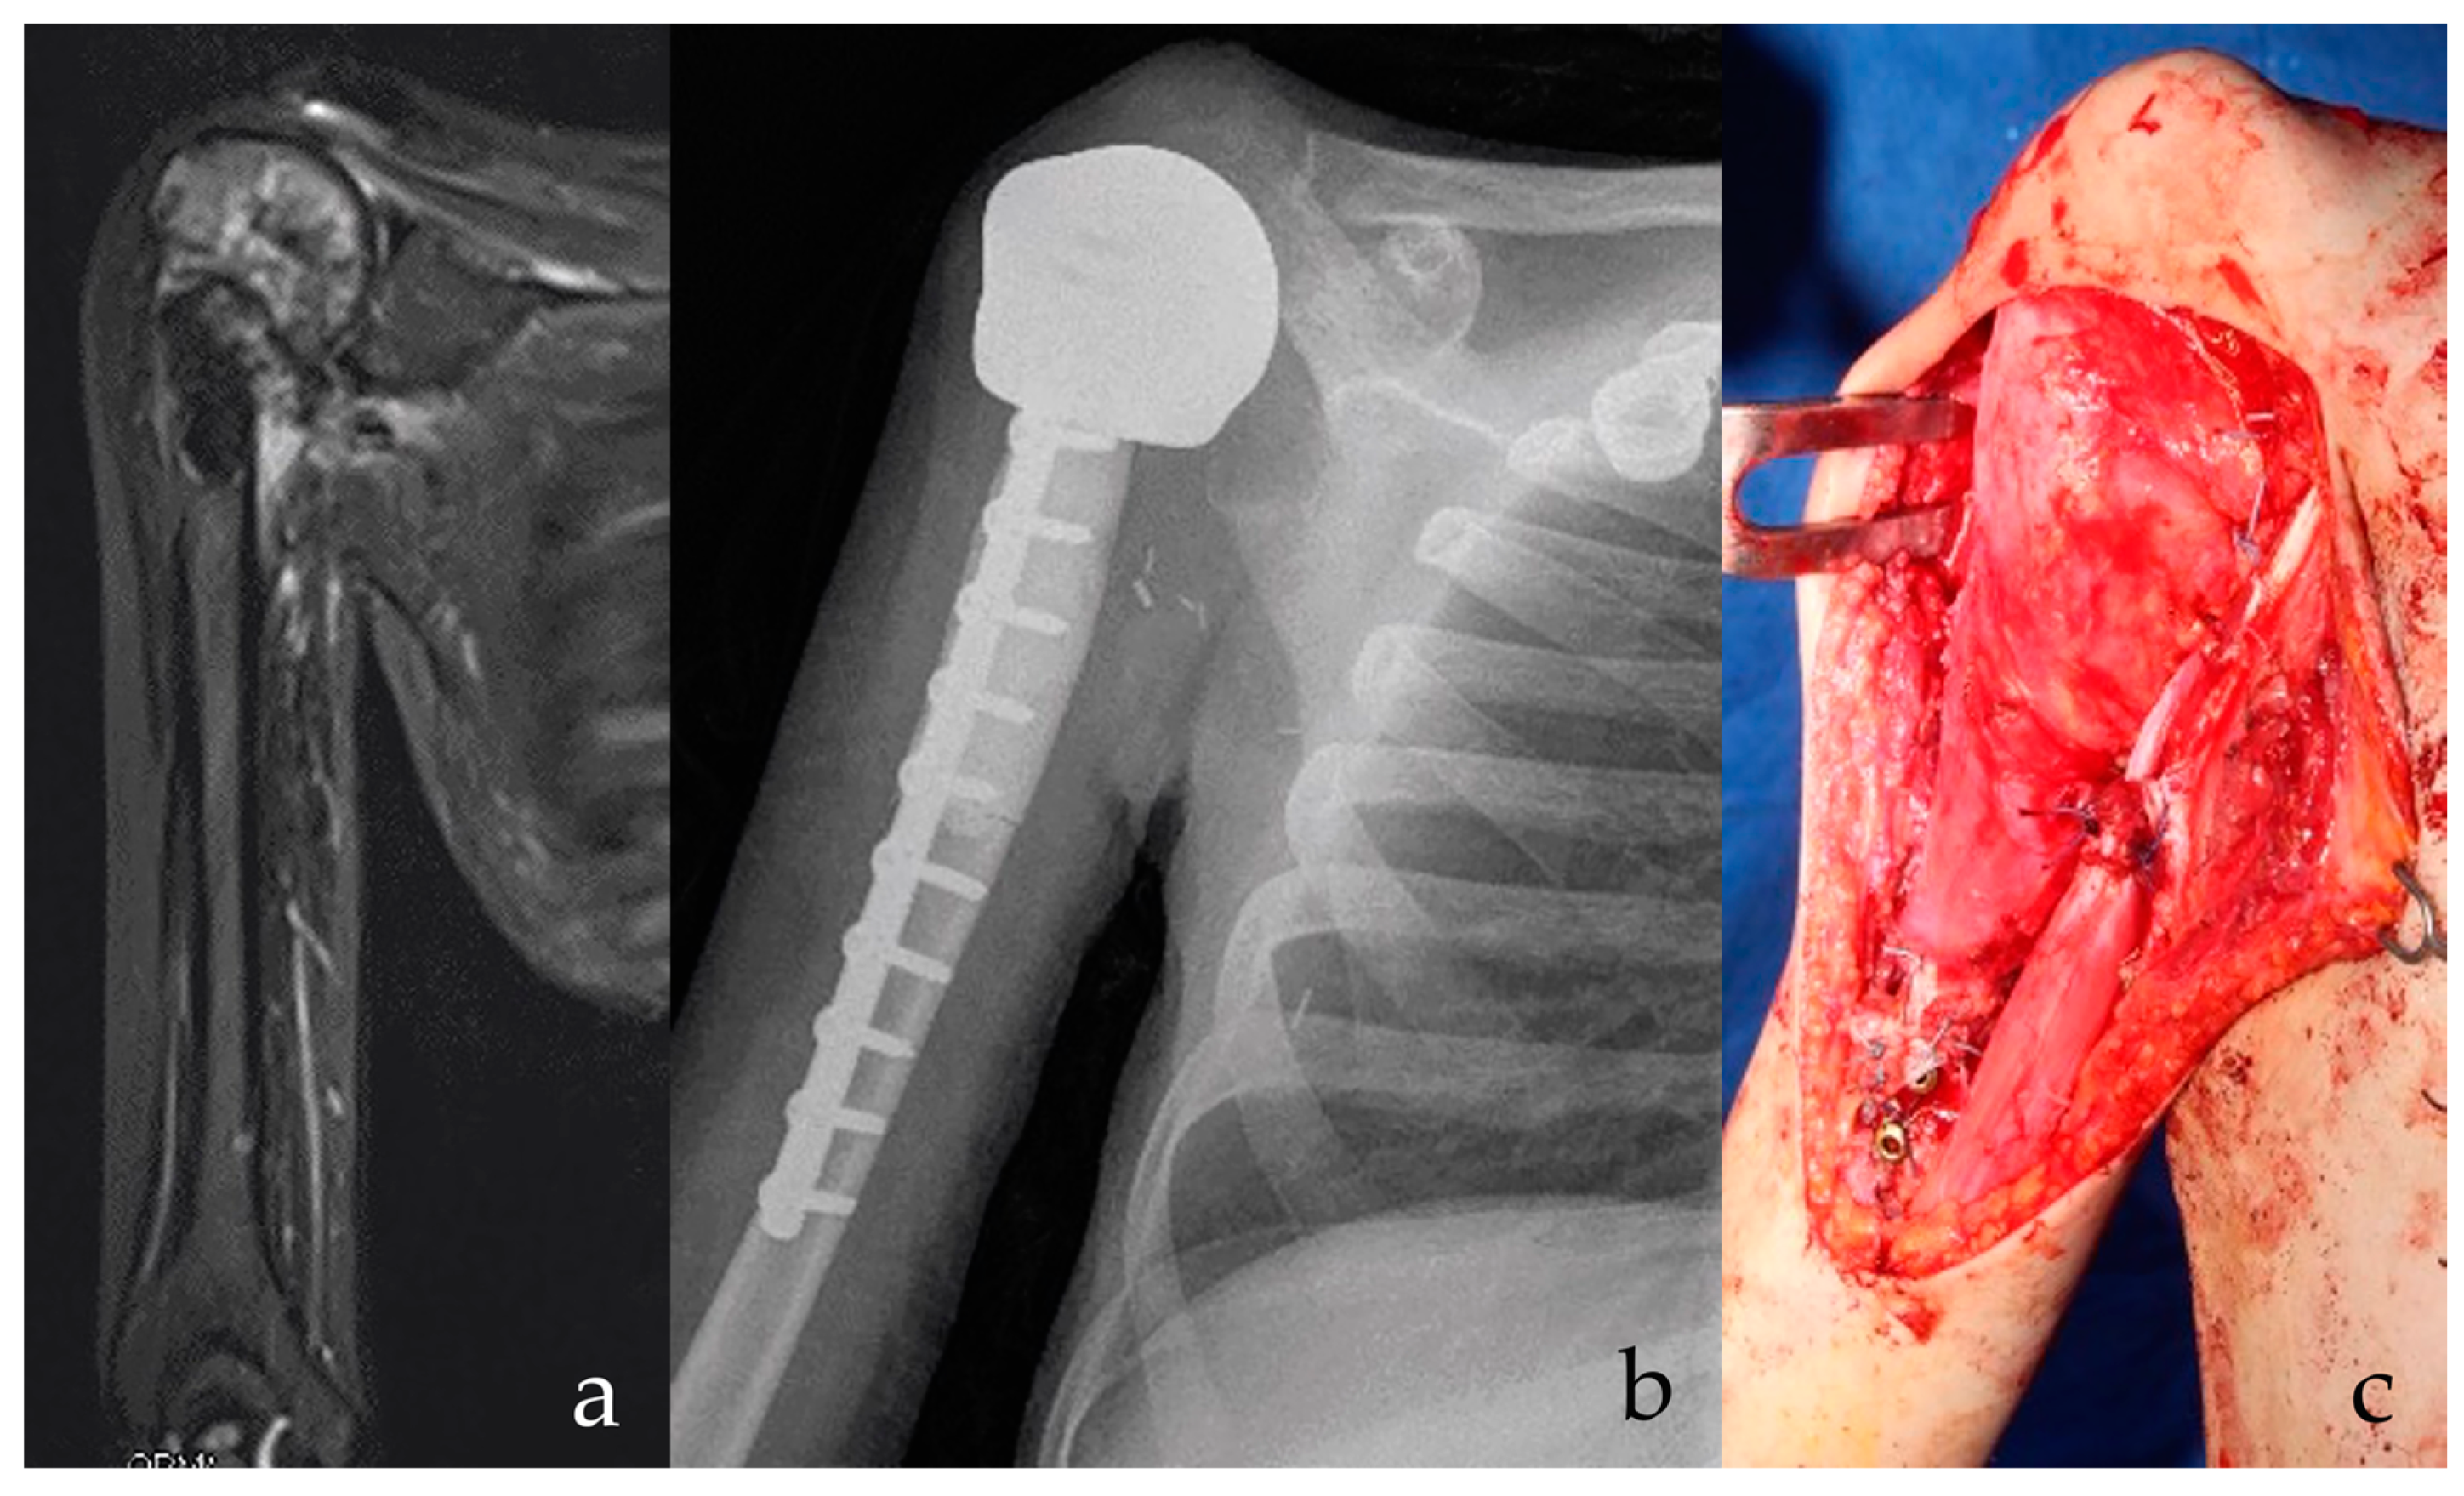

Figure 1.

(a) Osteosarcoma of the proximal humerus in Li Fraumeni Syndrome is shown on radiography. Possible infected biopsy tract. Patient had prior brain medulloepithelioma with residual parethic lower limb. Stable and effective shoulder function are essential for everyday activities. (b) After intraarticular proximal humerus and deltoid resection, a custom-made, 3D-printed anatomical proximal humerus reconstruction with diaphyseal antibiotic cement is implanted. At 15 months follow-up, the implant is stable. (c) A latissimus dorsi rotational flap provides for functional recovery of the deltoid and offers a biological barrier to infection. A stable and effective implant is shown, with low risks of secondary infection.